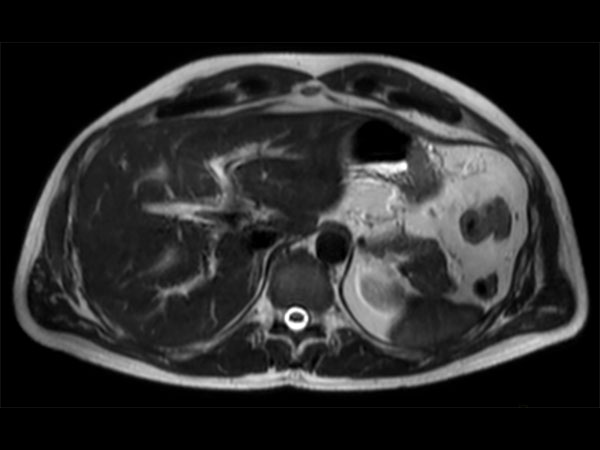

Advanced Liver MR - mDIXON Quant

University of Michigan Hospital, Ann Arbor, USA